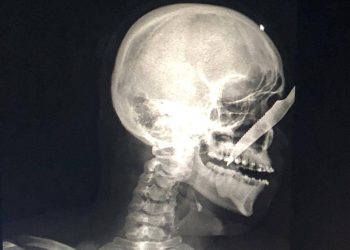

Jovem fica com faca cravada no nariz após ser atacado por bêbado no interior do AM

Um jovem identificado como Alberto Carvalho de Oliveira, de 25 anos, ficou com uma faca cravada no nariz após ser...